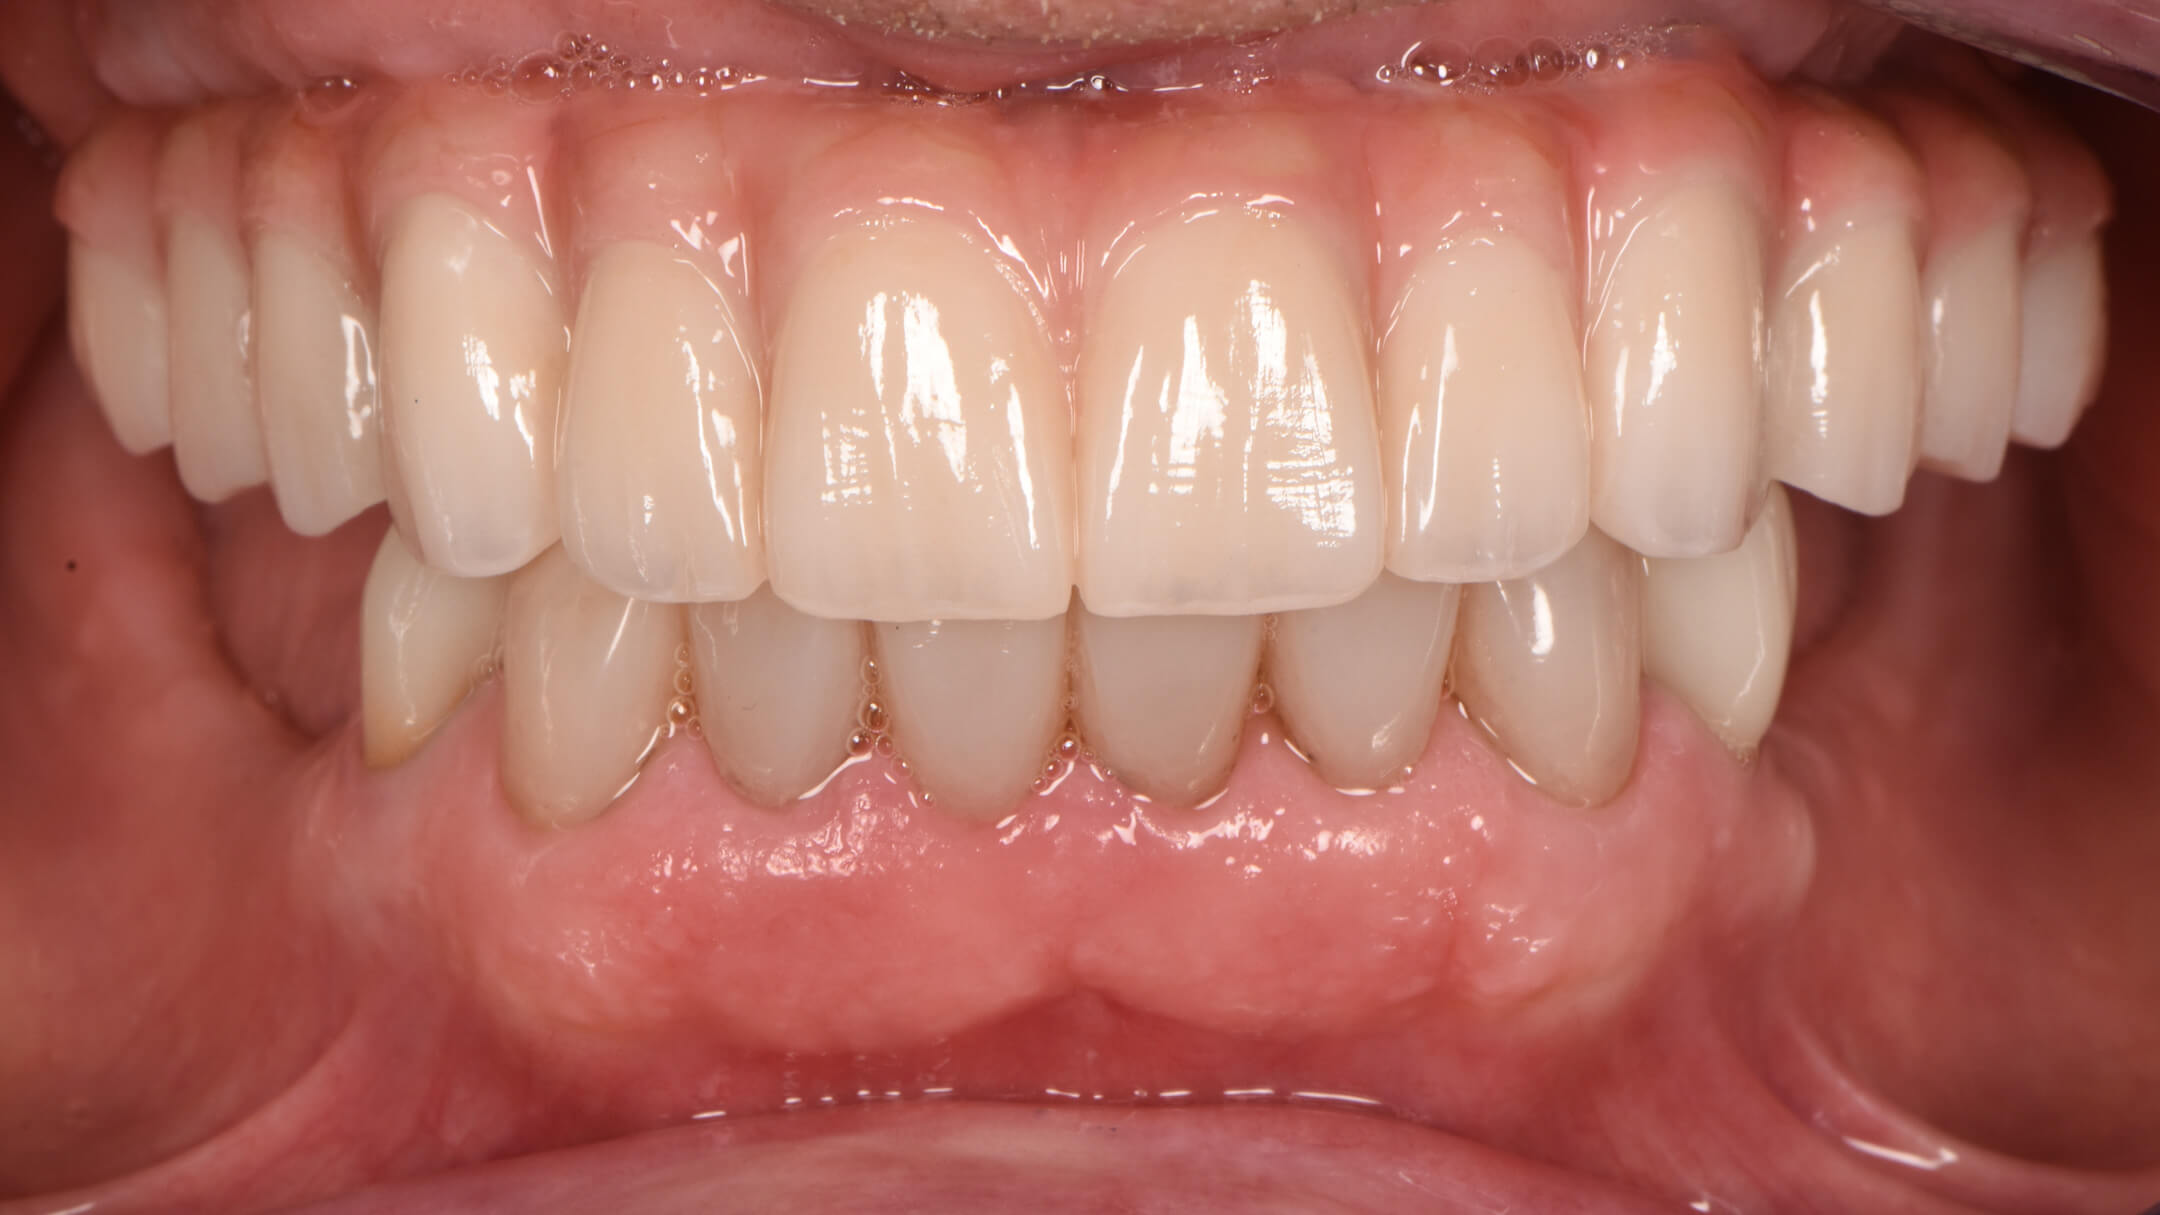

After